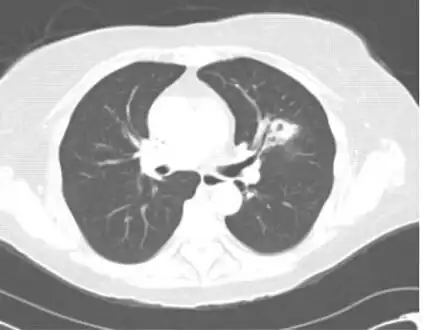

Chest computed tomography image showing left upper lobe cavitary lesion consistent with invasive pulmonary aspergillosis -

Pulmonary aspergillosis